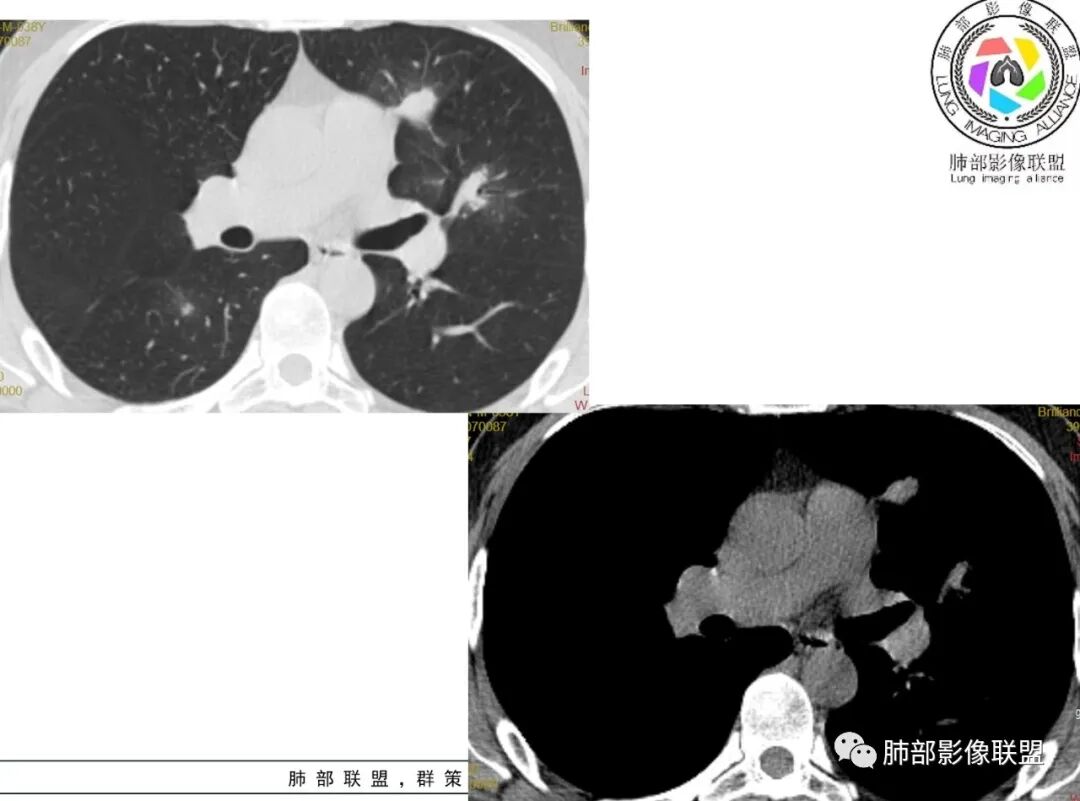

谢加平:左肺上叶和右肺下叶见多发散在性斑块病灶,边界清楚,部分见U形凹陷和刀切征,周围见模糊晕征,近胸膜下分布和蘑菇兄弟特点,累及左肺上叶上舌段支气管牵拉性扩张,前后13天复查整体病灶吸收不明显,有机化趋势表现,首选炎性肉芽肿(隐球菌感染?),请结合隐球菌荚膜抗原检查。

影像:左肺上叶、右肺下叶团片病灶,右肺下叶有结节病灶,病灶内支气管僵硬,稍扩张,强化有死

蓝天白云:两肺多发斑片状影,晕,内见扩张支气管影,可见直边,轻度延迟强化,纵隔肿大淋巴结,考虑炎性肉芽肿,隐球,淋巴瘤。

丽:双肺散在片状及结节状高密度影,边缘模糊,支气管穿行,走形僵硬,不均匀强化,考虑:OP,鉴别隐球菌,淋巴瘤。

小兜:男性,39岁,3周前劳累受凉史,次日至三亚开始咳嗽咳痰,入院时自述症状减轻。CT示双肺多发斑片影,部分病灶内部支气管壁增厚扩张穿行,平扫密度均匀,增强未见明显坏死,治疗前后部分病灶略吸收。实验室检查白细胞血沉轻度增高。考虑隐球菌感染可能,鉴别类鼻疽,淋巴瘤。

尘缘:中年男性,咳嗽咳痰伴乏力多汗,无发热,偶有畏寒。期间至某中医院治疗服中药后,症状好转。白细胞与血沉稍高。影像表现:左上肺团块状影(增强后CT值约22,伴有血管漂浮),中间支气管明显扩张,伴有小空洞形成,周围有晕,右下肺多发团块状影(增强后CT值约48),无明显支扩,伴胸膜下多发小结节,13天后复查,左上肺主病灶无明显变化,其他病灶范围有缩小,空洞消失,右下肺病灶变化不明显。

2、影像资料:双肺多发的小结节、斑片状及不规则型的实性病灶,周围有晕,沿支气管血管束分布,部分的病灶周围可见磨玻璃样影、支气管的扩张以及小的空洞。增强扫描病灶,轻度强化内部见支气管造影征。部分的病灶,支气管有扩张,内壁凹凸不平的改变,纵隔淋巴结未见肿大。病灶整体的形态还是多样化,部分位于胸膜下。